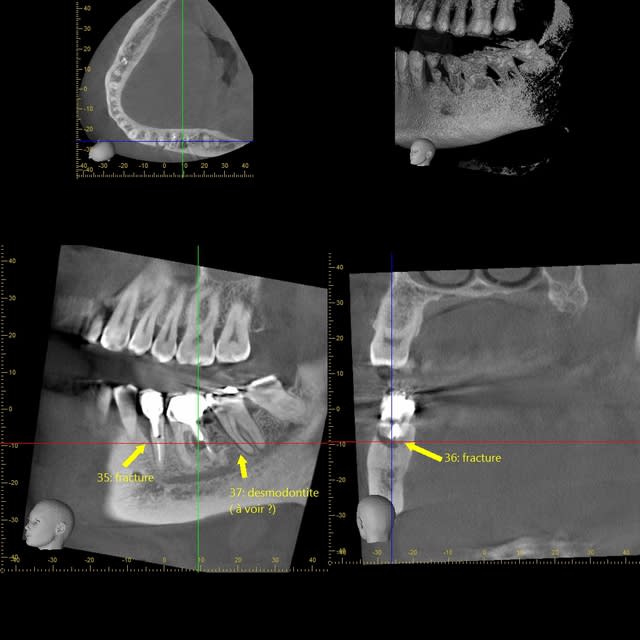

je viens de tomber sur une clé usb avec quelques images...

Guenfra i5kyps - Eugenol

Xyzview 20140607 112446 ida9qe - Eugenol

Xyzview 20140703 133108 osyuum - Eugenol

Volumerenderer 20140703 1331 wcokhm - Eugenol

Xyzview 20140619 122545 wt8h7c - Eugenol